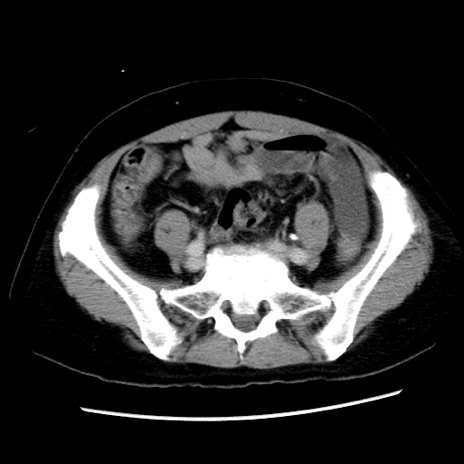

症例10(横断像)

【症例】 50歳代女性

【主訴】 腹痛

【現病歴】前日生レバーを食べた。今朝に排便あり。 昼前に突然発症の腹痛を生じ、当院救急外来を受診した。

【身体所見】 意識清明、腹部:平坦、軟、下腹部やや左を中心に圧痛・反跳痛あり、筋性防御あり

【データ】WBC 7800、CRP 0.07